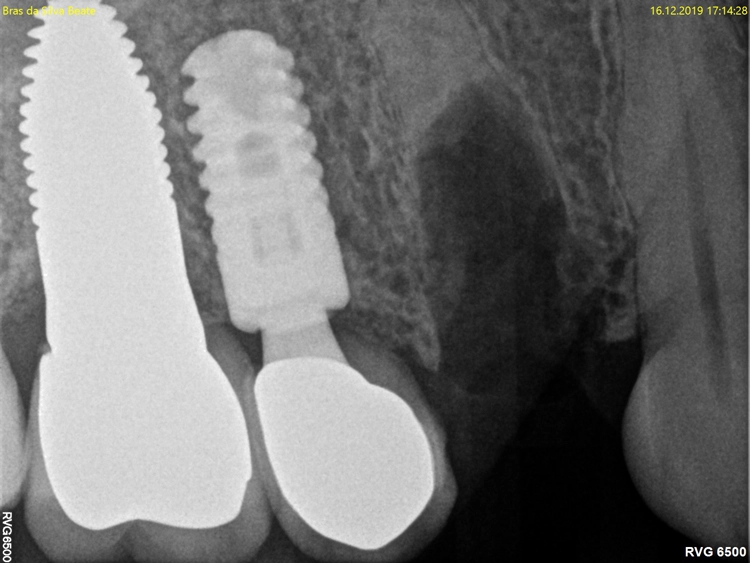

Kontrollbild und Röntgenkontrolle ein Jahr und ein Monat nach Socket/Ridge Preservation (Abb. 21 und 22). Der komplette Umbau zu Eigenknochen ist noch nicht abgeschlossen. Die Papillenregeneration zwischen 13/14 und 14/15 ist jedoch deutlich erkennbar.

Aufgrund der traumatischen Extraktion des ankylosierten Zahnes, die zu einer Osteotomie wurde (Abb. 3), fehlten die vestibuläre und palatinale Lamelle (Röntgenkontrollbild während der Osteotomie, Wurzelrest noch vorhanden Abb. 4). Dieser Wurzelrest wurde entfernt. Bei dem geringen Restknochenvolumen war eine Sofortimplantation nicht mehr indiziert.

Der Erhalt der Weichgewebsstrukturen und des Kieferkamms wurde durch das Einbringen eines Knochenaufbaumaterials im Sinne einer Socket/Ridge Preservation ohne Membran gewährleistet (Abb. 5). Mesial zum 13 wurde eine resorbierbare Naht (SABAsorb rapid) gesetzt, um die Weichgewebe zu adaptieren. Die Kontrolle des Heilungsverlaufs nach dem Eingriff erfolgte ein Tag später (Abb. 6).